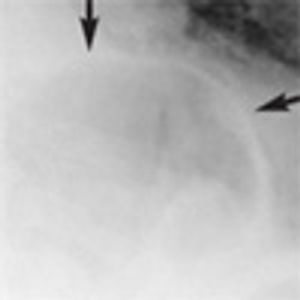

An 88-year-old woman was brought to the emergency department after she choked on a piece of meat. She had dysphagia of many years’ duration and progressive weight loss over the past 5 years.